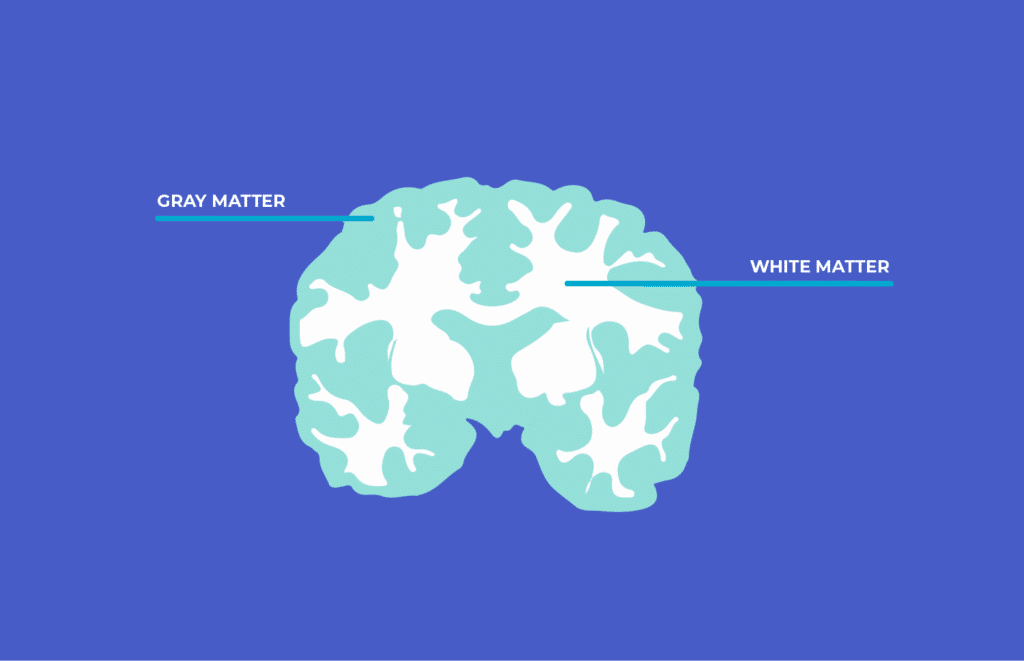

Unlocking Your Brain White Matter VS Grey Matter Muse EEG

Gray Matter vs White Matter Technology Networks new arrivals, Grey Matter vs White Matter in the Brain new arrivals, Brain Anatomy and How the Brain Works Johns Hopkins Medicine new arrivals, Gray and white matter of the brain MedlinePlus Medical new arrivals, White Matter and Your Brain new arrivals, What Is White Matter In The Brain new arrivals, Grey Matter Brain Damage White vs. Grey Matter Injury new arrivals, Grey and White Matter Physiopedia new arrivals, Brain Structure and Function Headway new arrivals, Neuroanatomy of the brain with respect to white matter inside the new arrivals, Why Is Gray Matter Gray Live Science new arrivals, Gray and white matter Organ Systems MCAT Khan Academy new arrivals, White matter The brain s flexible but underrated superhighway new arrivals, What Is White Matter In The Brain new arrivals, What do grey and white matter in the brain represent new arrivals, On Biology The subway of the brain Why white matter matters new arrivals, Why is the brain called grey matter Quora new arrivals, Grey Matter In The Brain new arrivals, Global hypomyelination of the brain white and gray matter in new arrivals, White matter Wikipedia new arrivals, Heard of the brain s gray matter Here s why the white matter is new arrivals, Gray and white matter new arrivals, Covalent Logic grey anatomy brainy facts about grey matter new arrivals, Unlocking Your Brain White Matter VS Grey Matter Muse EEG new arrivals, What is the link between white matter lesions and neurodegeneration new arrivals, What is new arrivals, Anatomy of the white matter tracts Video Anatomy Osmosis new arrivals, You have likely heard of the brain s gray matter here is why the new arrivals, Gray Matter and White Matter in the Brain new arrivals, neuroscience Why is the order of white grey matter different in new arrivals, 25 Brain facts you should know Brainscape Academy new arrivals, White Matter Wonders Re imagining the Brain s Silent Majority new arrivals, Vascular dementia explained Alzheimer s Research UK new arrivals, Volume of gray brain matter significantly lower in people with new arrivals, Even Mild Cases Of COVID 19 Can Leave A Mark On The Brain Such As new arrivals.

Gray Matter vs White Matter Technology Networks new arrivals, Grey Matter vs White Matter in the Brain new arrivals, Brain Anatomy and How the Brain Works Johns Hopkins Medicine new arrivals, Gray and white matter of the brain MedlinePlus Medical new arrivals, White Matter and Your Brain new arrivals, What Is White Matter In The Brain new arrivals, Grey Matter Brain Damage White vs. Grey Matter Injury new arrivals, Grey and White Matter Physiopedia new arrivals, Brain Structure and Function Headway new arrivals, Neuroanatomy of the brain with respect to white matter inside the new arrivals, Why Is Gray Matter Gray Live Science new arrivals, Gray and white matter Organ Systems MCAT Khan Academy new arrivals, White matter The brain s flexible but underrated superhighway new arrivals, What Is White Matter In The Brain new arrivals, What do grey and white matter in the brain represent new arrivals, On Biology The subway of the brain Why white matter matters new arrivals, Why is the brain called grey matter Quora new arrivals, Grey Matter In The Brain new arrivals, Global hypomyelination of the brain white and gray matter in new arrivals, White matter Wikipedia new arrivals, Heard of the brain s gray matter Here s why the white matter is new arrivals, Gray and white matter new arrivals, Covalent Logic grey anatomy brainy facts about grey matter new arrivals, Unlocking Your Brain White Matter VS Grey Matter Muse EEG new arrivals, What is the link between white matter lesions and neurodegeneration new arrivals, What is new arrivals, Anatomy of the white matter tracts Video Anatomy Osmosis new arrivals, You have likely heard of the brain s gray matter here is why the new arrivals, Gray Matter and White Matter in the Brain new arrivals, neuroscience Why is the order of white grey matter different in new arrivals, 25 Brain facts you should know Brainscape Academy new arrivals, White Matter Wonders Re imagining the Brain s Silent Majority new arrivals, Vascular dementia explained Alzheimer s Research UK new arrivals, Volume of gray brain matter significantly lower in people with new arrivals, Even Mild Cases Of COVID 19 Can Leave A Mark On The Brain Such As new arrivals.